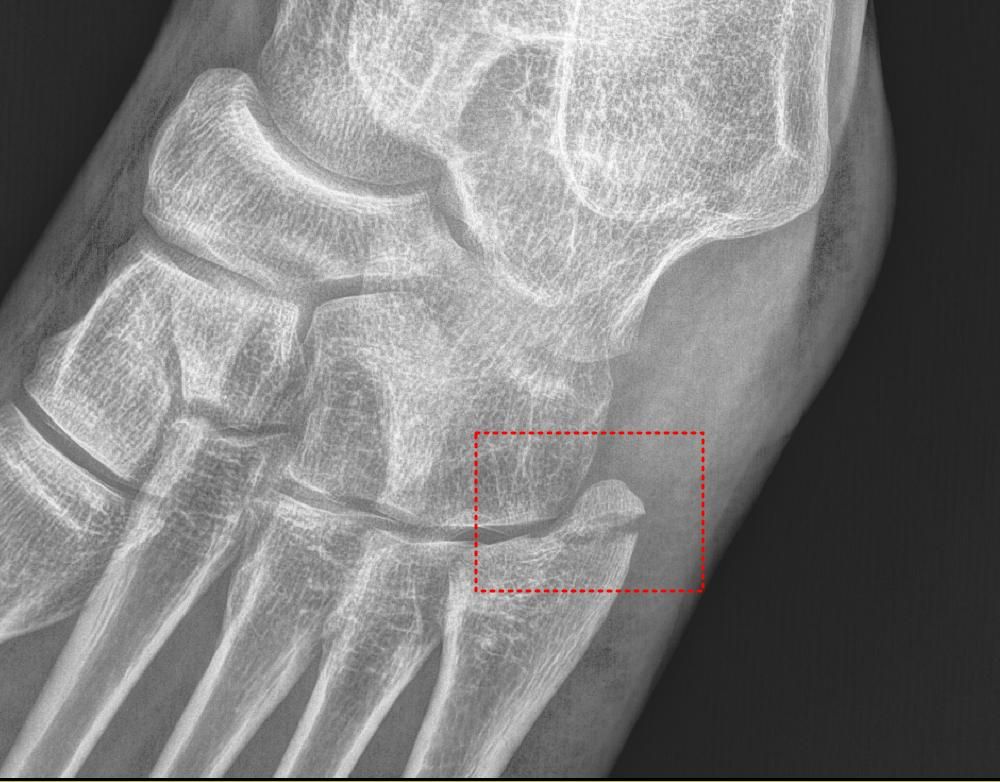

5번 중족골 기저부 골절 수술여부 판단

• 1번 째 사진

5번 중족골 기저부 골절에 따른 수술 여부는 단순 주상골 골절인 같은 인대가 뼈를 잡아당기면서 생기는 골절이나 미세한 골절이면 비수술적 치료도 충분히 가능하나 비체중부 골절이나 분쇄골절 시에는 자연 회복이 어렵기 때문에 수술이 필요할 수 있는 상황입니다.

사진상으로는 골절 부위가 뼈의 중심에서 다소 떨어져 있으며, 일부 변위도 있는 것으로 보입니다.

비수술적인 치료도 고려될 수 있지만 아무래도 수술을 하시는게 회복기간 및 예후가 좋을 것으로 생각됩니다.